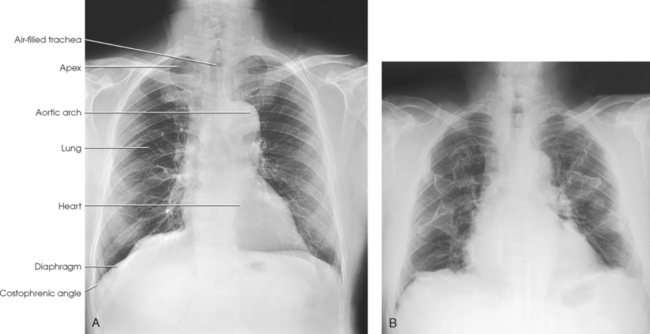

Fig. 10-30 Expiration in the same patient as in Fig. 10-29 (posterior rib numbers).

Structures shown: PA projection of the thoracic viscera shows the air-filled trachea, the lungs, the diaphragmatic domes, the heart and aortic knob, and, if enlarged laterally, the thyroid or thymus gland (Fig. 10-32). The vascular markings are much more prominent on the projection made at the end of expiration. The bronchial tree is shown from an oblique angle. The esophagus is well shown when it is filled with a barium sulfate suspension.